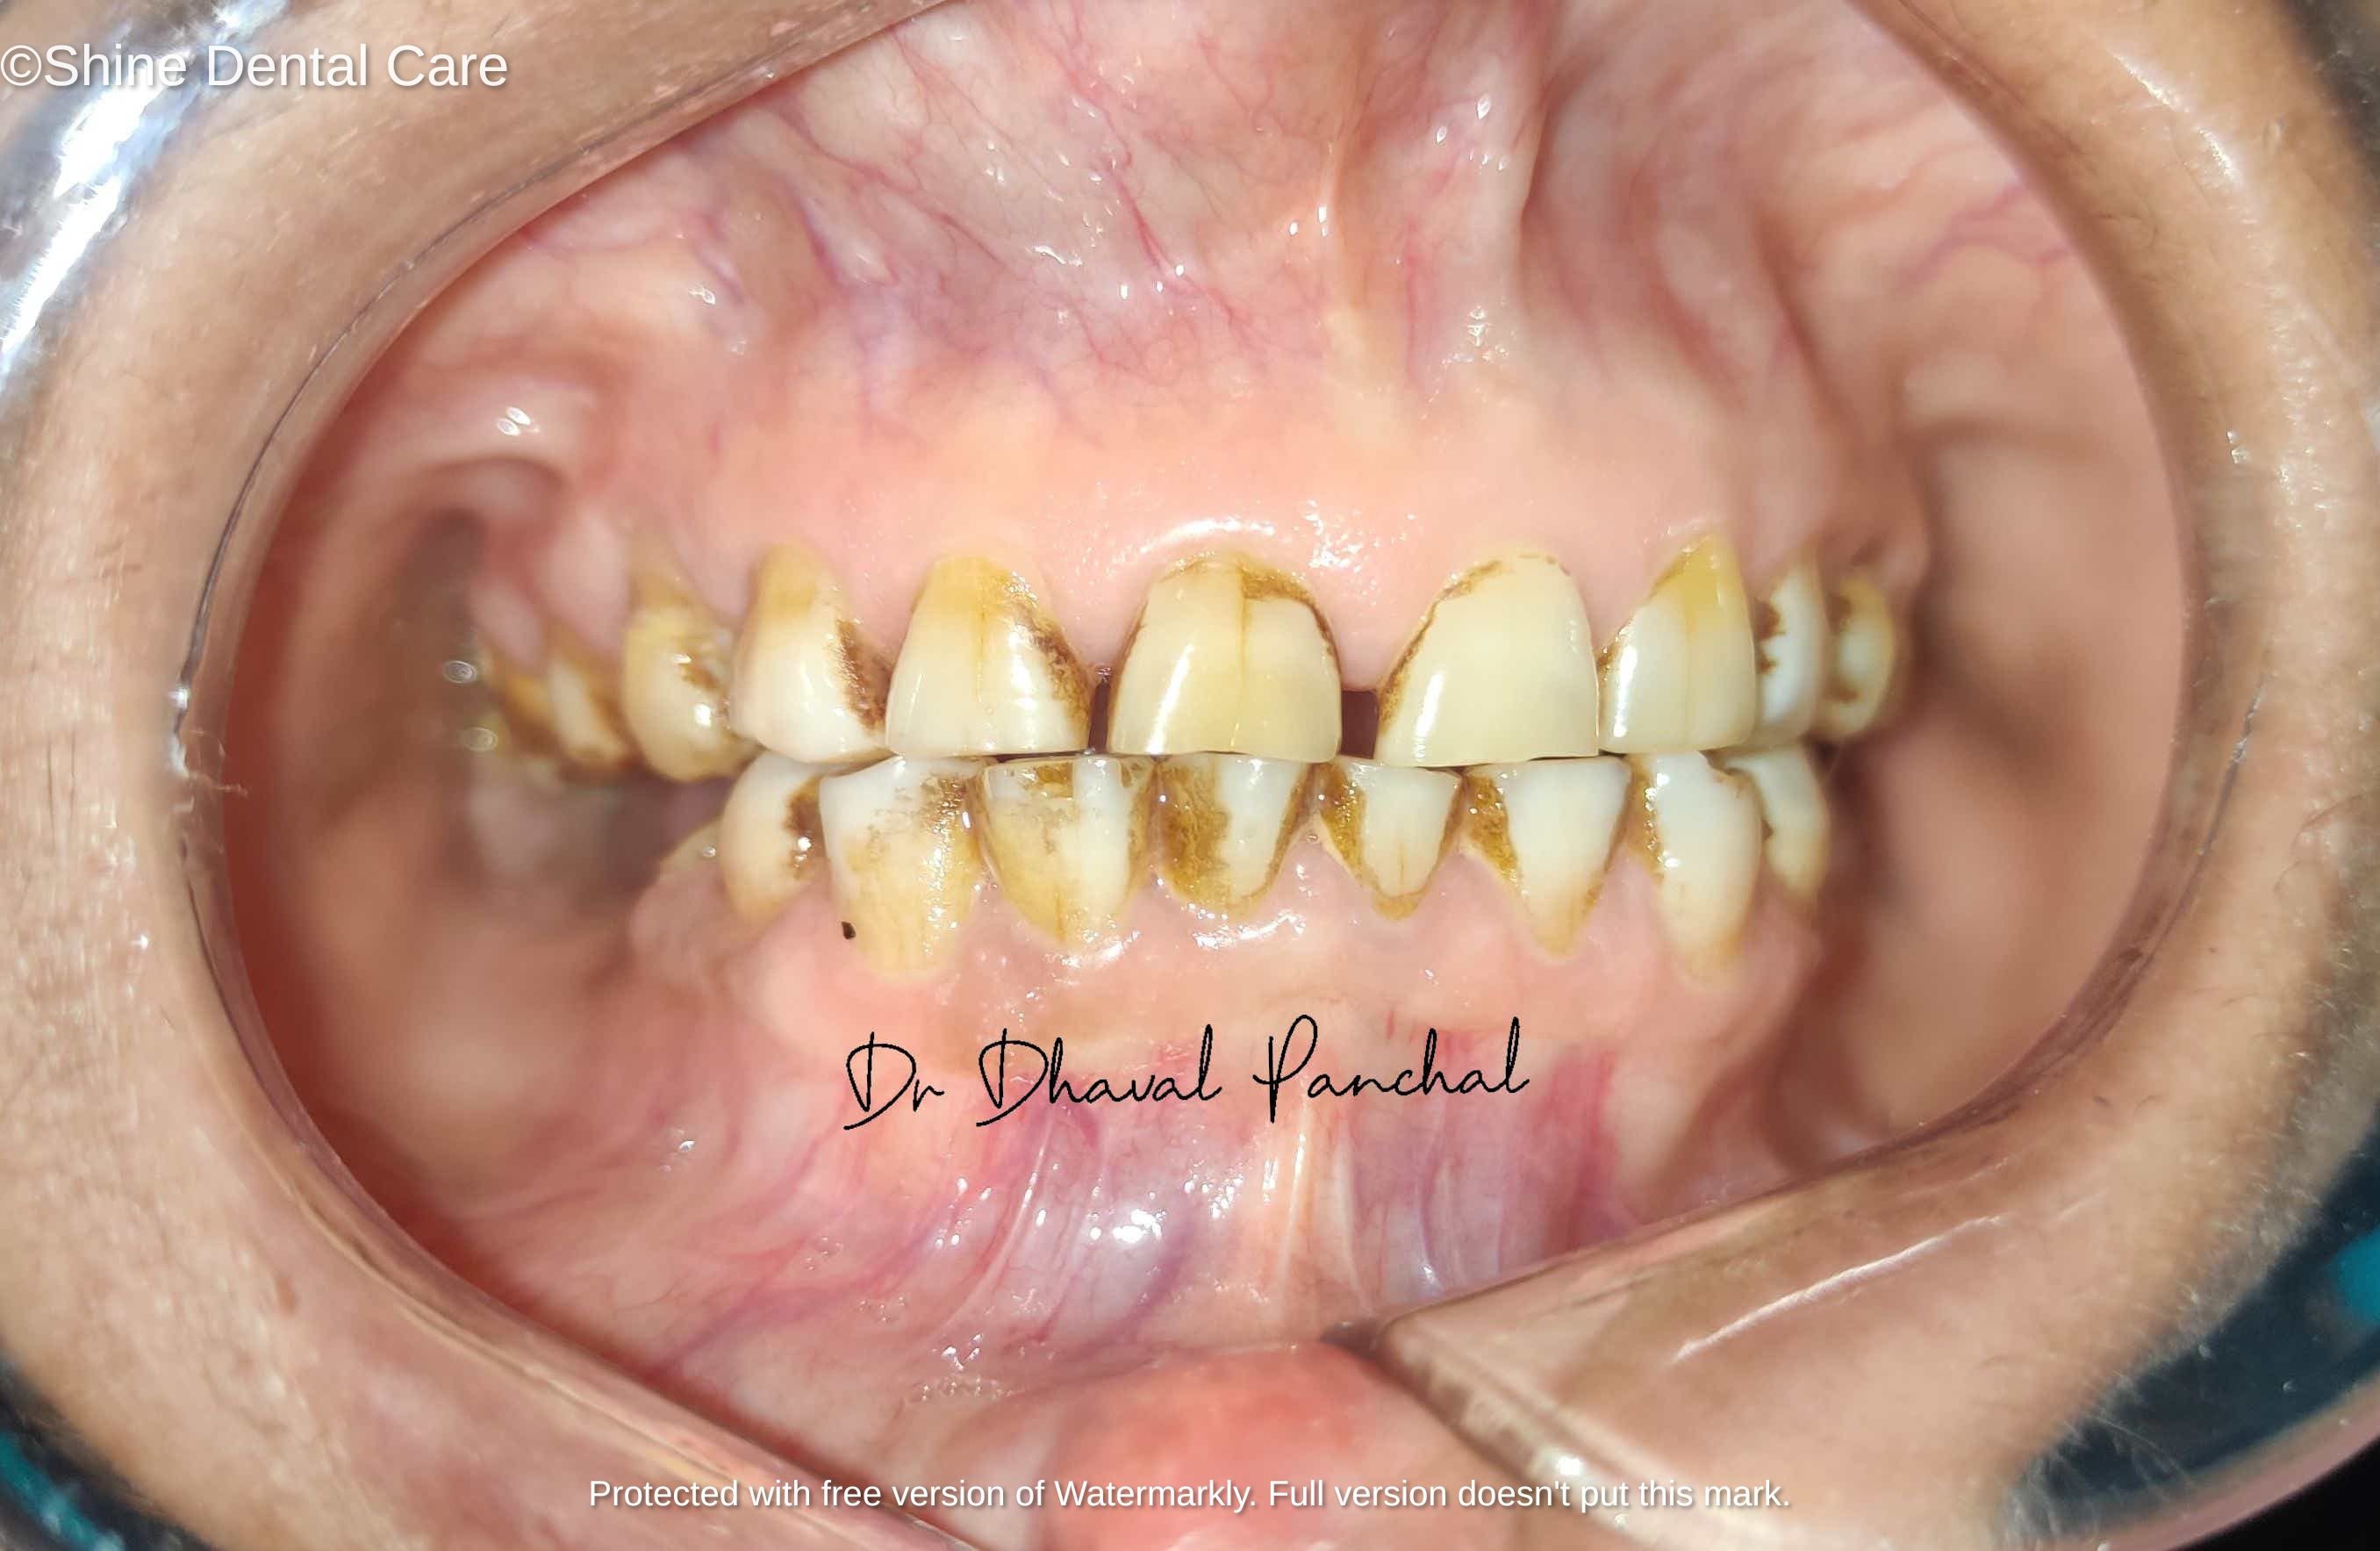

Full Mouth Rehabilitation

As the name implies, Full Mouth Rehabilitation refers to rebuilding and/or replacing all of the teeth ina patient’s mouth. Full Mouth Rehabilitations combine esthetics with the science of restorative dentistry to improve the health, function, and beauty of the mouth.

There are a number of people who have dental problems throughout their mouths that must be treated comprehensively with a vision of a final result that improves both function and esthetics. These patients may exhibit multiple missing teeth, numerous teeth with large fillings that are failing or exhibiting decay, cracked or broken teeth, or badly worn teeth due to bruxism (teeth grinding) or other habits.